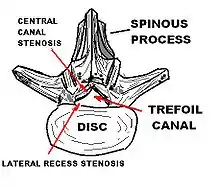

| Lumbar vertebra showing central stenosis and lateral recess stenosis. | |

Spinal stenosis may be congenital (rarely) or acquired (degenerative), overlapping changes normally seen in the aging spine.[6][7] Stenosis can occur as either central stenosis (the narrowing of the entire canal) or foraminal stenosis (the narrowing of the foramen through which the nerve root exits the spinal canal). Severe narrowing of the lateral portion of the canal is called lateral recess stenosis. The ligamentum flavum (yellow ligament), an important structural component intimately adjacent to the posterior portion of the dural sac (nerve sac) can become thickened and cause stenosis. The articular facets, also in the posterior portion of the bony spine can become thickened and enlarged, causing stenosis. These changes are often called "trophic changes" or "facet trophism" in radiology reports. As the canal becomes smaller, resembling a triangular shape, it is called a "trefoil" canal.